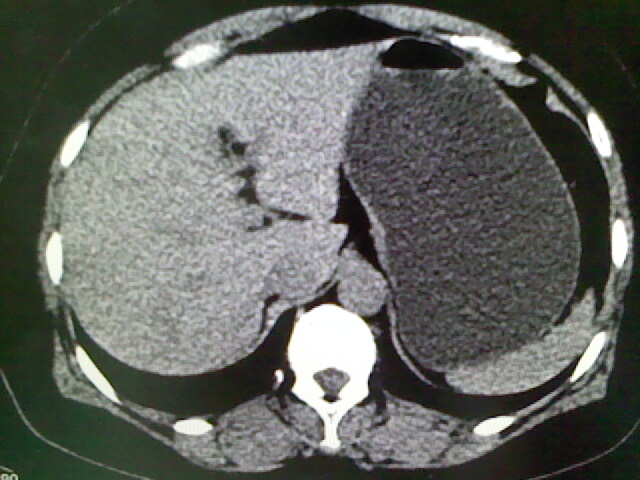

以下是引用卜一在2009-4-2 13:26:00的发言:[br]胆囊颈部结石伴胆囊炎!另:建议增强,待除外肝内占位及胆囊占位!

以下是引用liaoqiang在2009-4-2 16:23:00的发言:[br]胆囊是否切除?胆囊颈区致密影考虑金属夹?结石?肝脏右叶低密度影,考虑增强。